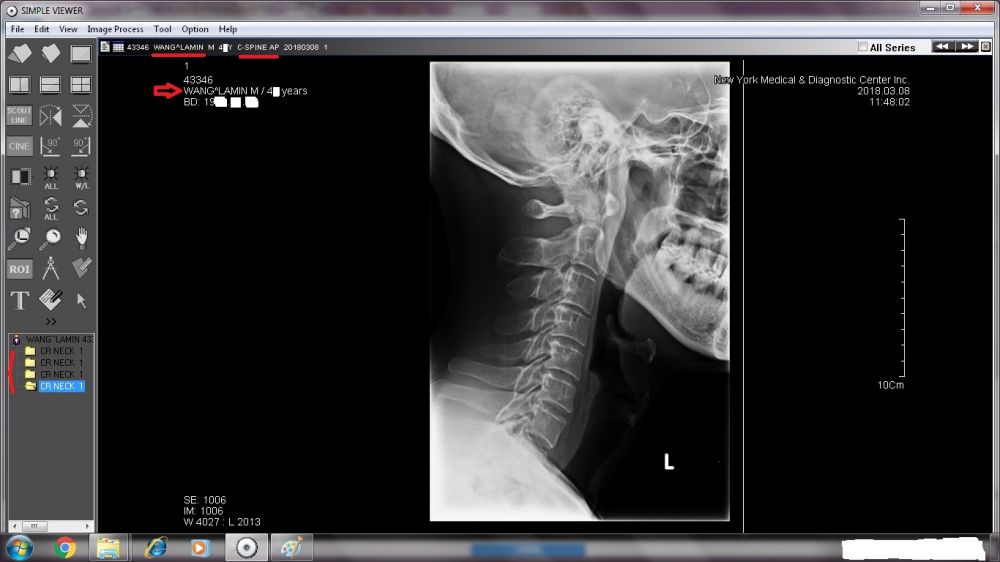

A TREMENDOUS amount needs to be revealed. Right now, I will start with the two sets of X-ray images done by New York Medical & Diagnostic Center (80-46 Kew Gardens Rd, Kew Garden, NY 11415. Tel: (718) 261-1000 ).